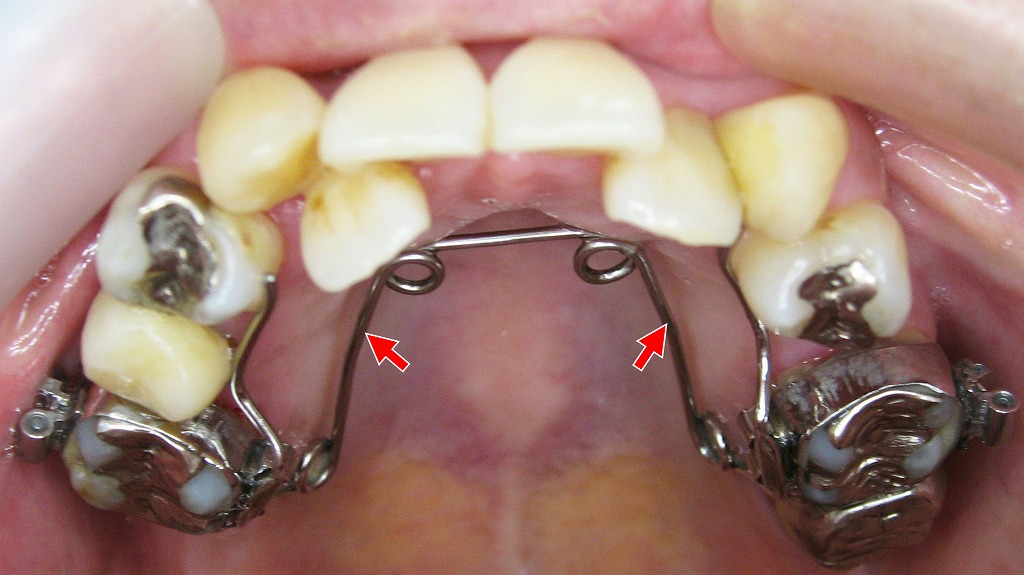

クワドヘリックス(Quad Helix)は、上顎の歯列を横方向に拡大するために使われる固定式の矯正装置です。金属製のワイヤーが4つのループ(ヘリックス)状に加工され、上顎の第一大臼歯に装着されたバンドに固定されます。この装置はワイヤーの弾性を活かして、持続的な圧力を歯と骨に加え、歯列の幅をゆっくりと広げていきます。

クワドヘリックスは、第一大臼歯にセメントで固定された金属バンドと、ループ状のワイヤーによって構成されています。このワイヤーに事前に広がる形状の「テンション(力)」を加えて装着することで、歯列の内側から持続的な力を歯と骨に与え、拡大が始まります。

ワイヤーの弾性が常に力を発生させているため、患者の装着時間に左右されず、計画通りの拡大力を得やすいのが特徴です。

- 🪛 上顎の第一大臼歯に金属バンドを固定

- 🌀 ワイヤーに事前に広げたテンションを加えて装着し、拡大がスタート